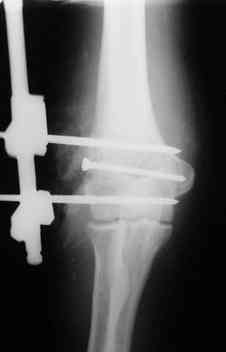

Открытый чрезмыщелковый перелом плеча |

Уважаемые коллеги! Мужчина, 49 лет, упал 2 недели назад, будучи около полугода в запое. Сразу припоступлении рана промыта а-ля пульсирующая струя" до 8 литров и стабилизация (без ушивания раны). Через 2 дня пациент покинул отделение, думаю, что сражался с рогатыми животными, еще через 4 дня победив всех врагов пришел как путный с поникшей головой. На настоящий момент рана с обильным гнойным отделяемым в виде комков, но повязка стала промокать меньше, температура субфебрильная 4 дня и выше 37,3 не поднималась, боли умеренные, больше ночью. Есть несколько вопросов: 1.Нужна ли сейчас ревизия и дебридмент? 2.Оптимальный вариант дренирования? (сейчас просто резиновые выпускники, в т.ч. через онтраппертуру). 3.Нижний стержень находиться в очаге. Его необходимо убрать? Если да, то вариант фиксации.Жалко свою работу. Может общими усилиями спасем? ;) Спасибо. С уважением, Алексей.

Если нет нагноения его канала, то убирать его не надо. Однако фиксация не сильно надежная, может, хоть задней гипсовой шиной дополнить. Или наложить секцию на предплечье.

Ув. коллега, как обстоят дела на данный момент (спустя 20 дней). Есть риск, что поплывет винт. Возможно, лучшим вариантом было ввести две спыцы и оставить их накожно, что-бы в случае войны убрать.

Уважаемые коллеги. Внешний вид конечности через 5 недель после травмы. Рана гранулирует, отделяемое скудное. Прошу строго не судить за внешний вид АВФ: ну нет пока у нас параллельных зажимов (приходиться выкручиваться).